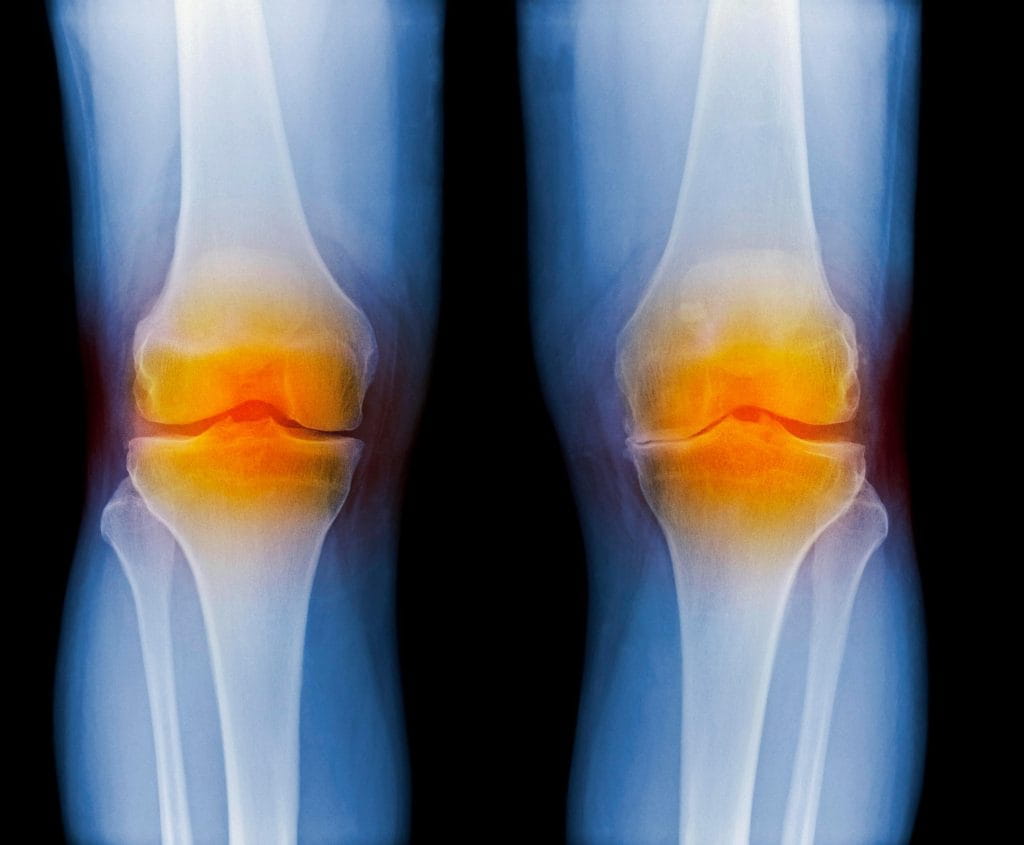

Супрапателлярный импиджмент коленного сустава: симптомы и лечение